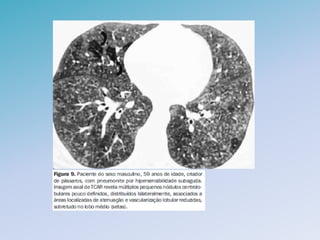

PNEUMONIA ORGANIZANTE CRIPTOGÊNICA

• Bronquiolite Obliterante com Pneumonia em Organização IDIOPATICA

• Evolução subagudo a crônico

• Não fumantes (2:1), ambos sexos e com media de 55 anos

• Quadro clinico

– Astenia, perda ponderal, mialgia e febre (50%)

– Dispnéia e tosse são frequentes

– EC localizados ou bilaterais

• Teste de Função Pulmonar: padrão restritivo e redução da DLCO

• RX: consolidacao de carater migratorio e recorrente

• TCAR

– Consolidação subpleural ou peribroncovascular (90%)

– Vidro fosco (60%)

• LBA: diferencial com infecção; linfocitose com ↓ CD4/CD8

• Diagnóstico histológico é necessário

– Infiltrado inflamatório alveolar e bronquiolar , sem destruição da

estrutura pulmonar subjacente

PNEUMONIA ORGANIZANTE CRIPTOGÊNICA •Bronquiolite Obliterante com Pneumonia em Organização IDIOPATICA • Evolução subagudo a crônico • Não fumantes (2:1), ambos sexos e com media de 55 anos • Quadro clinico – Astenia, perda ponderal, mialgia e febre (50%) – Dispnéia e tosse são frequentes – EC localizados ou bilaterais • Teste de Função Pulmonar: padrão restritivo e redução da DLCO

PNEUMONIA ORGANIZANTE CRIPTOGÊNICA •RX: consolidacao de carater migratorio e recorrente • TCAR – Consolidação subpleural ou peribroncovascular (90%) – Vidro fosco (60%) • LBA: diferencial com infecção; linfocitose com ↓ CD4/CD8 • Diagnóstico histológico é necessário – Infiltrado inflamatório alveolar e bronquiolar , sem destruição da estrutura pulmonar subjacente • TTO – Pode haver resolução espontânea (casos assintomáticos) – Prednisona 1mg/kg/dia por 3 meses + manutenção por 1 ano